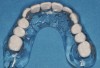

Figure 15  Fixed provisional bridge supported by the maxillary second molars and canines.

Figure 15